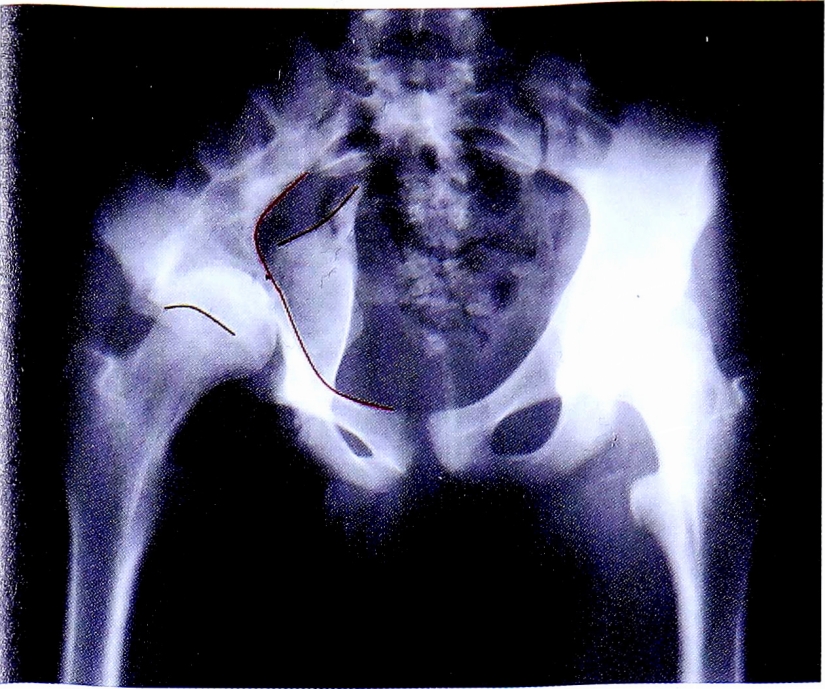

Следует отметить, что в данном примере (рис. 27) имеется повреждение линии заднего края, что соответствует повреждению задних отделов впадины. Однако повреждение этой линии в одном месте и, соответственно, отсутствие отдельного фрагмента задней стенки позволяет с большой долей вероятности исключить те типы переломов, при которых он наблюдается, а именно: перелом задней стенки и перелом задней колонны, ассоциированный с переломом задней стенки.

Рис. 27. Второй этап определения перелома задней колонны.

Fig. 27. Second step of posterior column fracture diagnostic.

Таким образом, методом исключения неповрежденных структур вертлужной впадины, диагностирован перелом задней колонны вертлужной впадины. Повреждение подвздошно-седалищной линии и деформация контуров запирательного отверстия подтверждает этот диагноз (рис. 28). На рентгенограмме в косой запирательной проекции определяется задний вывих головки бедренной кости и отсутствие отдельного фрагмента задней стенки (рис. 29).

Рис. 28. Верификация перелома задней колонны.

Fig. 28. Verification of posterior column fracture.

Рис. 29. Рентгенограмма в косой запирательной проекции.

Fig. 29. Obturetor oblique view.